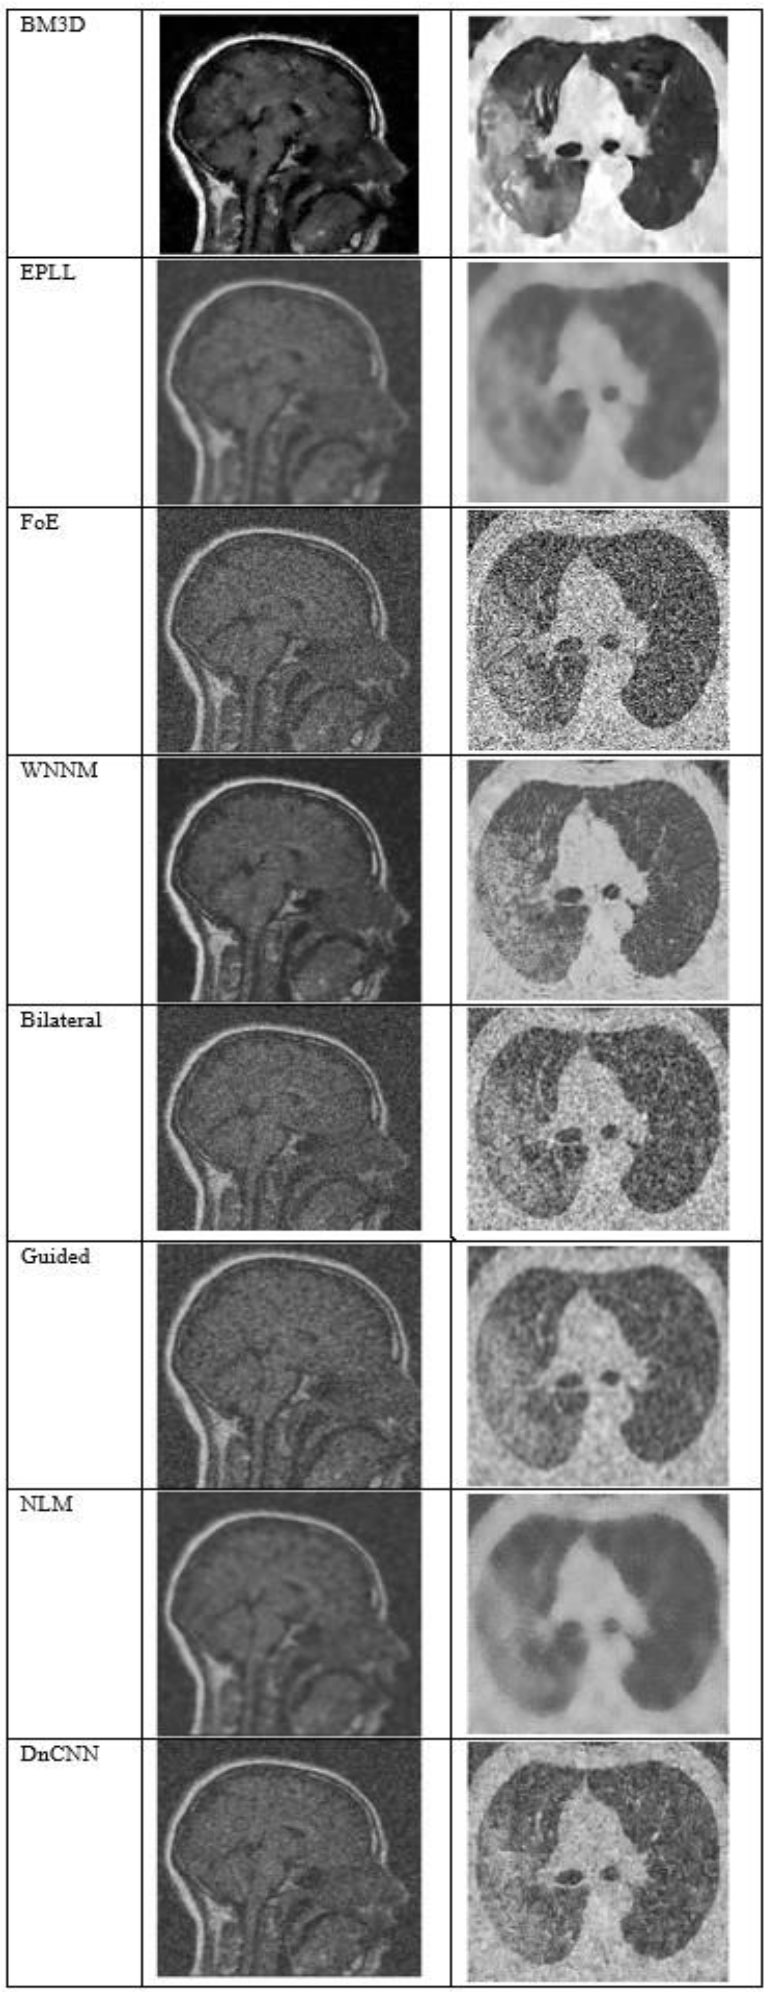

Fig. (4) shows the results at a noise variance of 0.01, where it has been observed that all algorithms produce clear images, except for the Guided algorithm.

Fig. (5) shows the results at a noise variance of 0.05, where it has been observed that the BM3D, EPLL, and WNNM algorithms produce clearer images compared to other algorithms. NLM and DnCNN also perform well, but not as well as the above-mentioned three algorithms.

The output of different algorithms at a noise variance of 0.01.

The output of different algorithms at a noise variance of 0.05.

Fig. (6) shows the results at a noise variance of 0.09, where it is observed that the BM3D, EPLL, and WNNM algorithms produce clearer images compared to other algorithms. Another algorithm, DnCNN, also performs well, but not so well as the above-mentioned three algorithms.

The output of different algorithms at noise variance 0.09.

Fig. (7) shows the results at a noise variance of 0.5, where it has been observed that all the algorithms produce blurred images, except for the BM3D algorithm. However, the results of the BM3D algorithm are not so satisfactory. As a result, it has been observed that at a noise variance of 0.5, none of the algorithms performed well.

The output of different algorithms at Noise Variance 0.50.